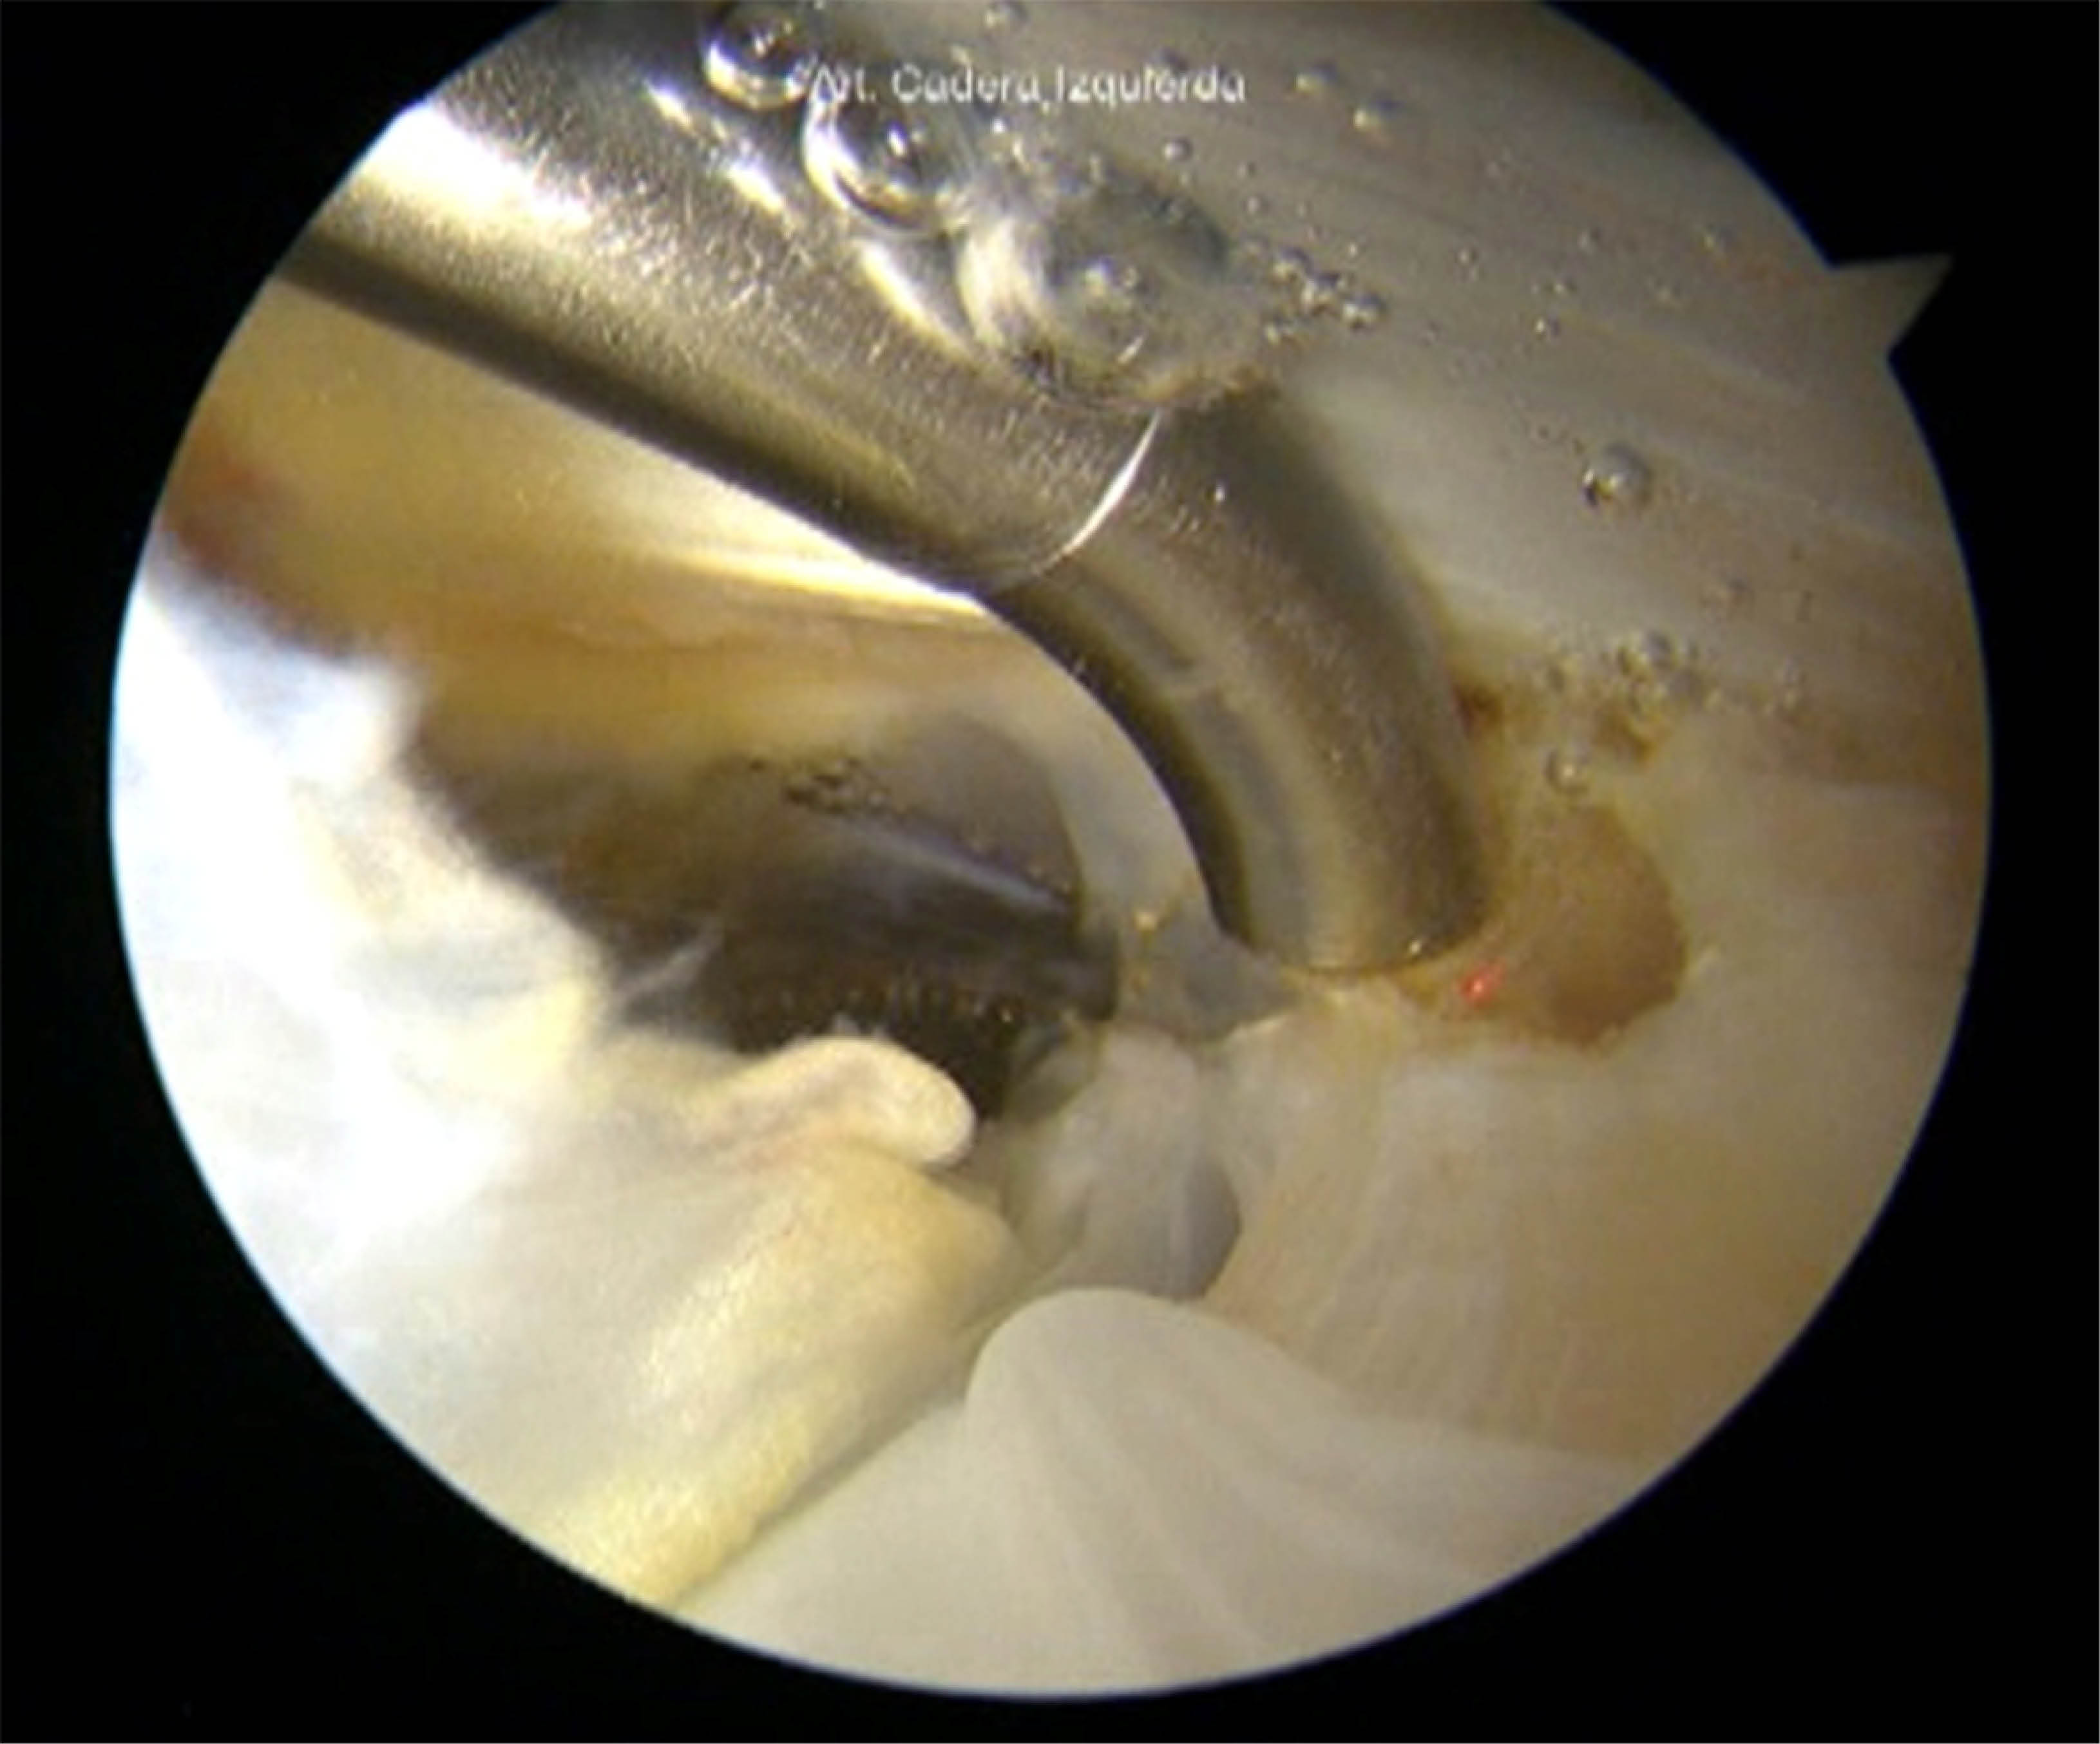

Liberación endoscópica del glúteo mayor para la descompresión peritrocantérica

Introducción: el síndrome peritrocantérico, también conocido como síndrome de dolor del trocánter mayor, afecta al 10-25% de la población y provoca dolor y deterioro funcional en la región lateral de la cadera. Esta afección suele estar asociada a discapacidades significativas a largo plazo. Objetivo: este estudio tiene como objetivo presentar un nuevo enfoque quirúrgico para el tratamiento del síndrome peritrocantérico que minimiza la invasividad y mejora los resultados para los pacientes. Material y métodos: describimos una técnica que utiliza portales personalizados a través de la banda iliotibial (BIT) junto con la liberación de la inserción proximal del glúteo mayor (GM). Los pacientes se colocan en posición supina, con acceso al espacio peritrocantérico mediante un artroscopio de 70°. Se realiza una liberación por radiofrecuencia de aproximadamente 3-4 cm de la inserción distal del GM para aliviar la presión y reducir la fricción en el espacio peritrocantérico. Conclusión: el método quirúrgico propuesto ofrece una alternativa prometedora a los enfoques tradicionales para el tratamiento del síndrome peritrocantérico, ya que minimiza el traumatismo tisular y mejora la recuperación. Es necesario realizar más investigaciones para evaluar la eficacia y la seguridad a largo plazo de esta innovadora intervención en una población de pacientes más amplia.

Figura 1